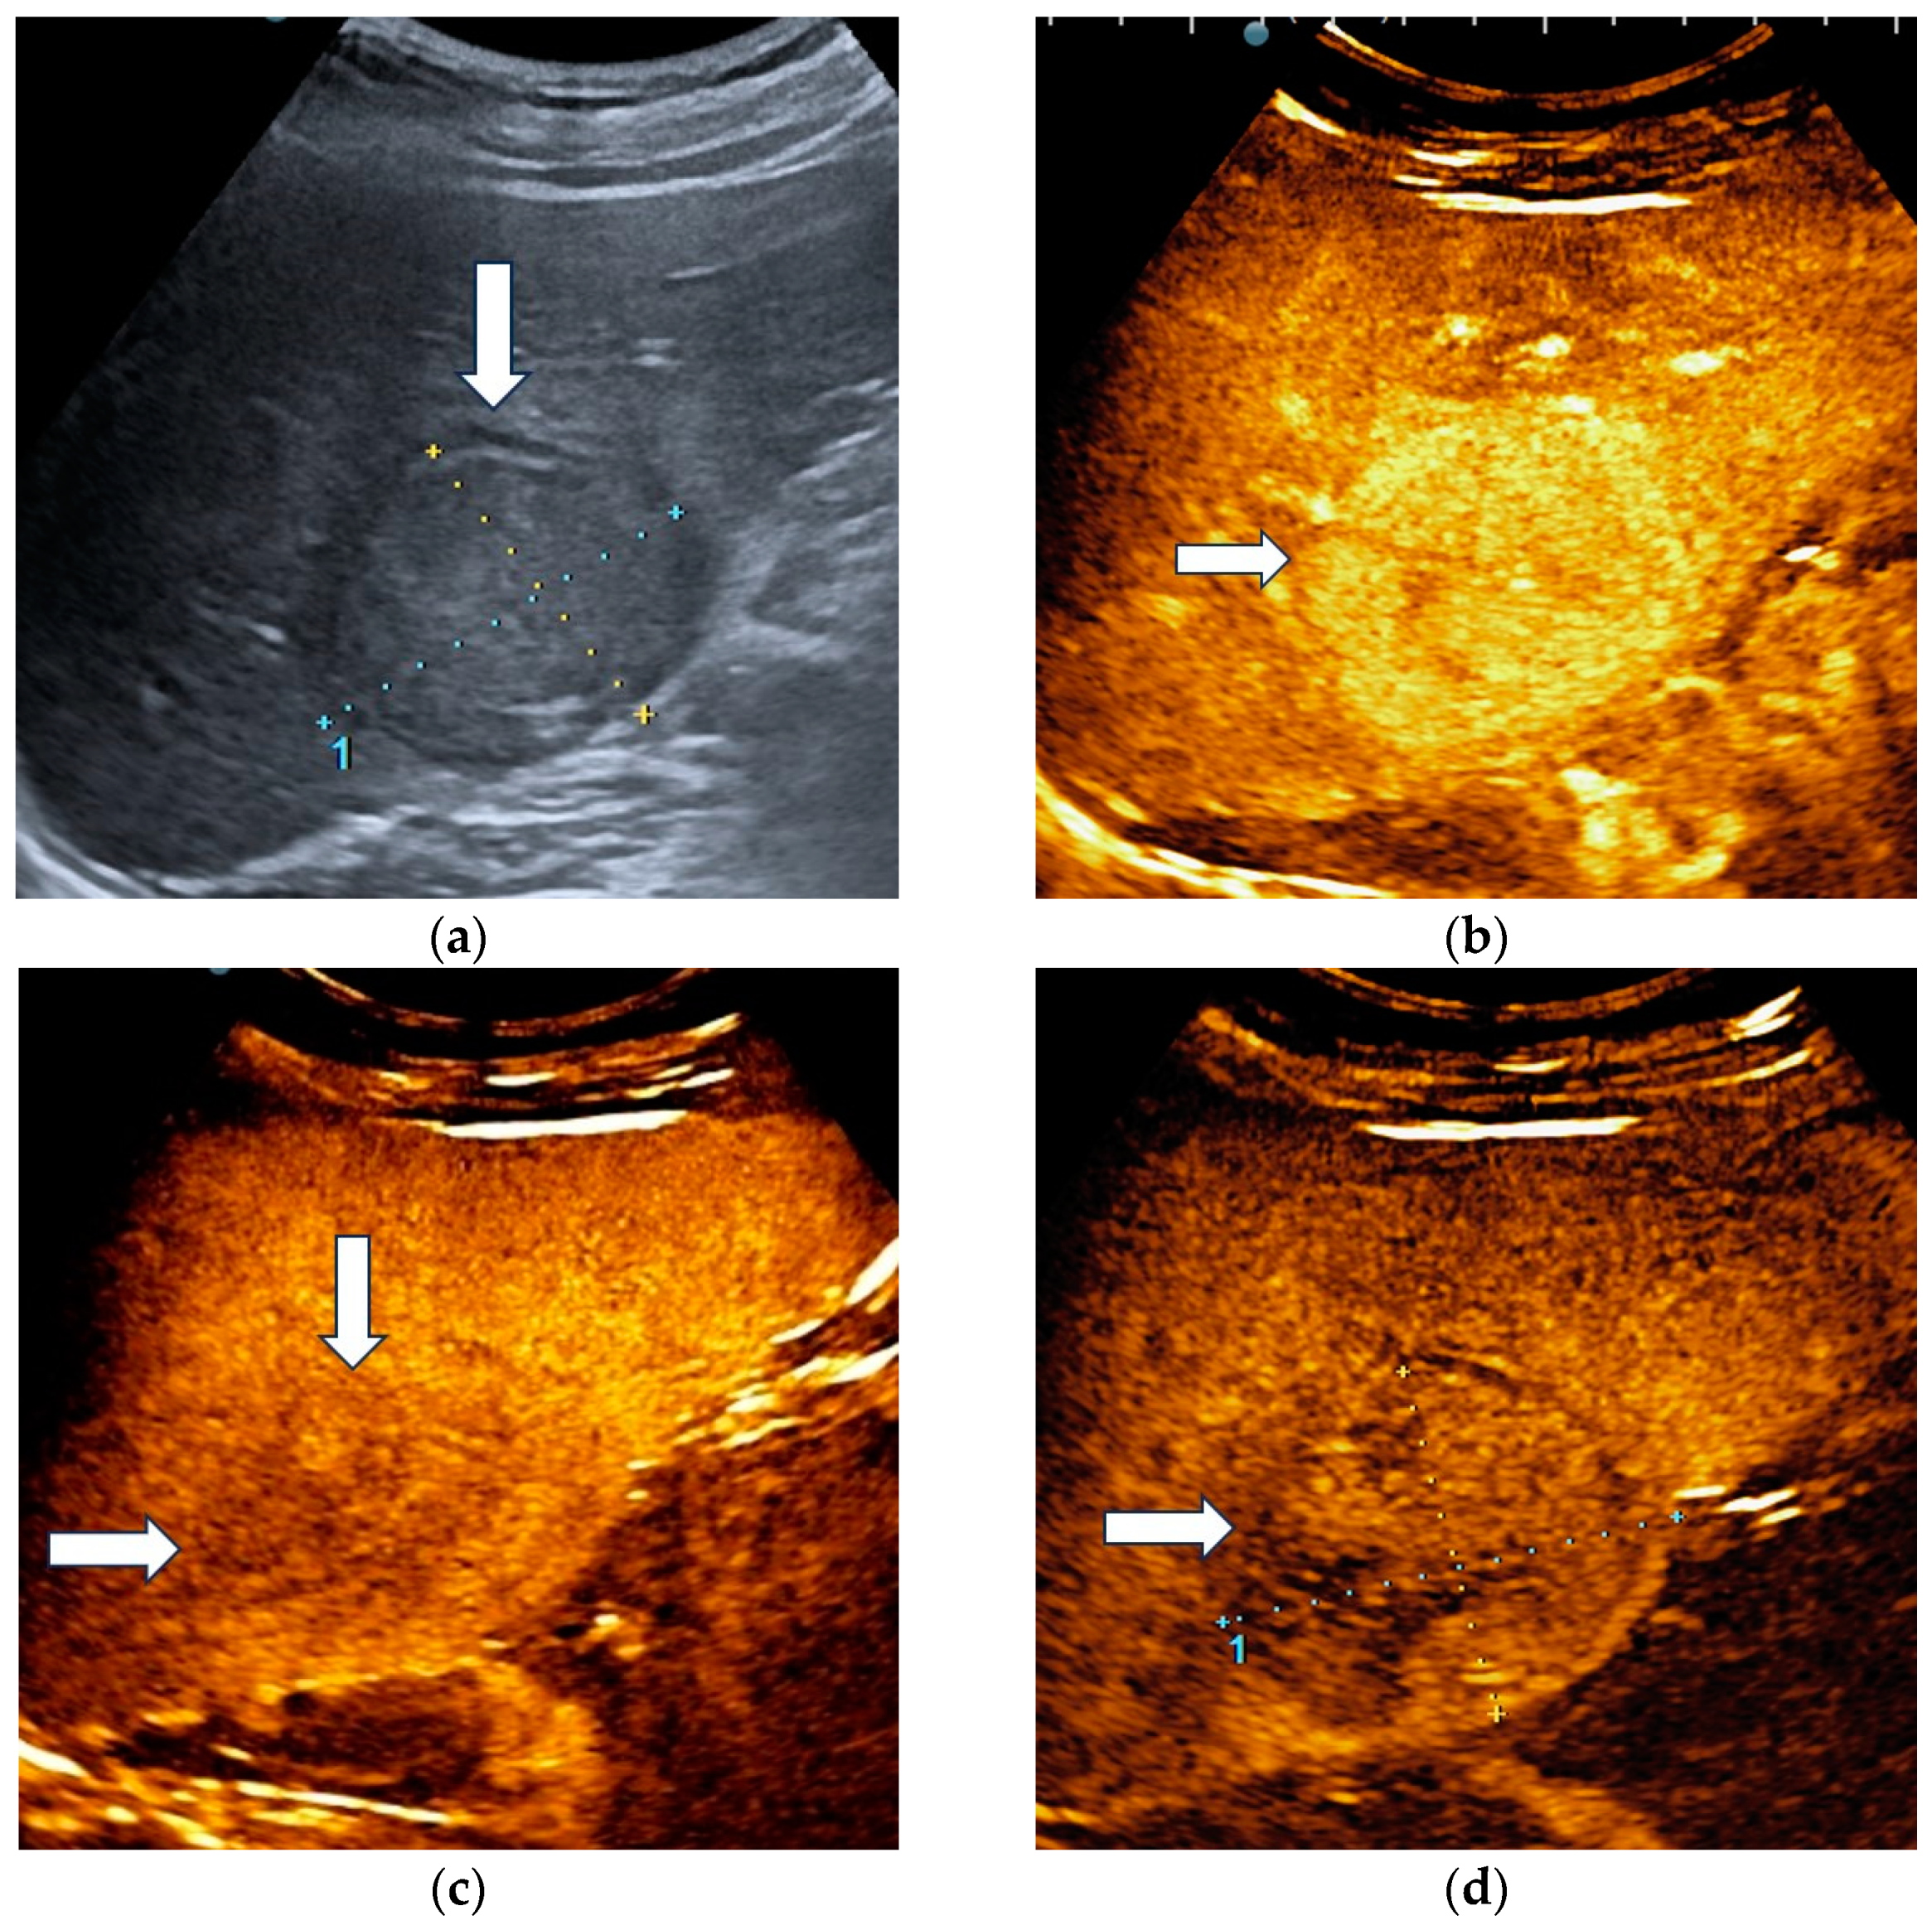

Hepatocellular adenoma demonstrated homogenous hyperenhancement in the arterial phase, followed by isoenhancement in the portal venous phase and became slightly hypoenhanced in the late phase, at more than 4 min after contrast agent injection (Figure 2).

Figure 2.

Misclassified liver adenoma by both readers and the AI system. B-mode ultrasound showed an isoechoic lesion (arrows) with a size of 23 mm, located in the right hepatic lobe (a). On CEUS, the lesion showed homogenous arterial hyperenhancement (arrows) (b), followed by isoenhancement in the portal venous phase (arrows) (c), with mild washout in the late phase (arrows) (d). Due to the presence of washout in the late phase, liver adenoma was misdiagnosed as a malignant tumor by both readers and the AI system.